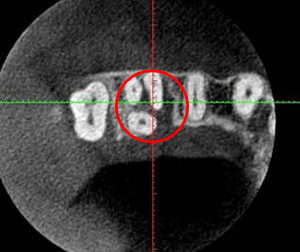

CT画像です。内側から分岐部まで破壊されいます。外側の骨は破壊されていません。 |